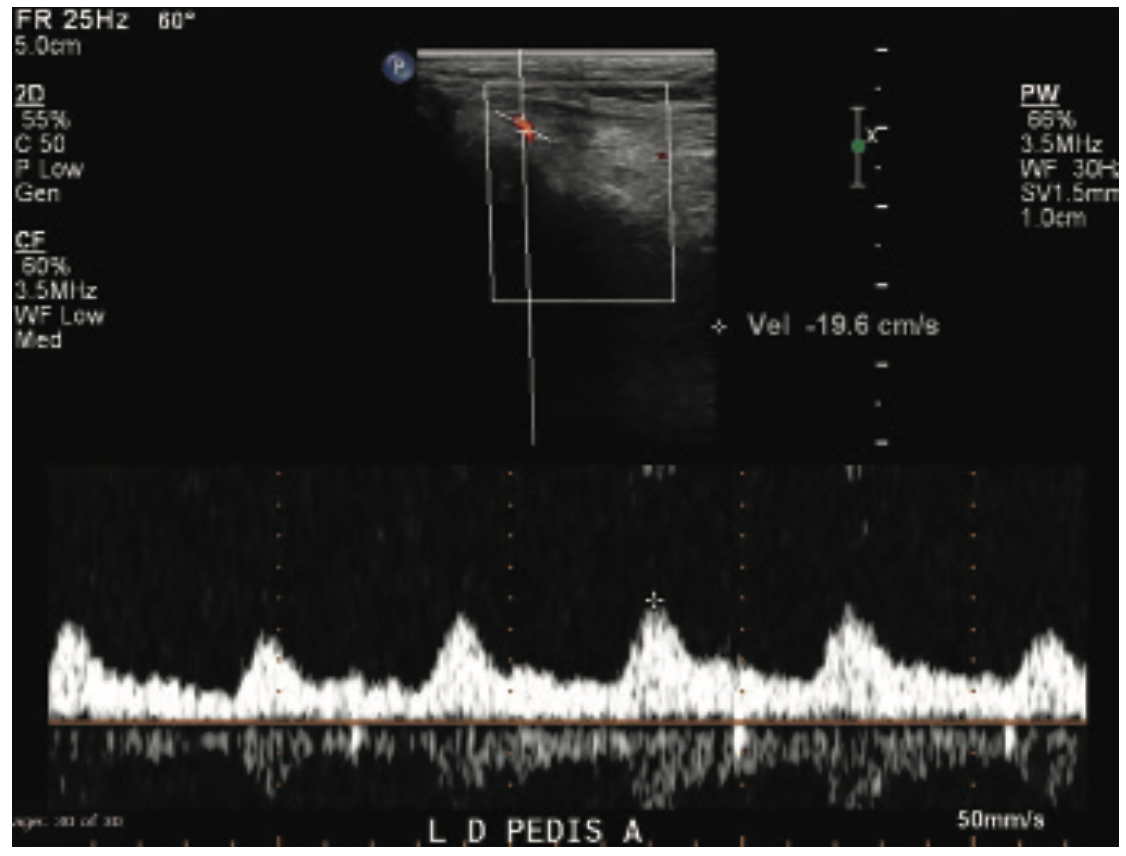

This is a 71-year-old male with a prior history of aortic valve replacement on coumadin, peripheral arterial disease, myocardial infarction, diabetes, and chronic kidney disease. He presented with a 3-month history of ischemic rest pain involving the left lower extremity, no wounds. He had previously undergone left superficial femoral artery (SFA) stenting for a chronic occlusion, but despite this, continued to have rest pain with peroneal-only runoff (Figures 1-4). He was brought in for left anterior tibial artery recanalization.

This patient had significant tibial disease involving the ostia of the vessels. He didn’t have wounds, but he did have rest pain. There are two reasons this patient was a good candidate for the MicroStent and the SOBE balloon protection technique: the tibioperoneal trunk was open so there was a way to cross the origin of the AT, and size-wise, it was a 3 mm vessel (and the bigger, the better, with the tibials). As Dr. Jihad Mustapha has reported, tibial sizing is important, whether confirmed angiographically or by intravascular ultrasound (IVUS). The anatomy was good; there was a short lesion at the anterior tibial origin and we were able to cross that area to put up the balloon in order to protect the origin. The stent had a perfect landing. In general, when I place tibial stents, it is nice to have a focal, shorter lesion, because patency tends to be better in that situation.